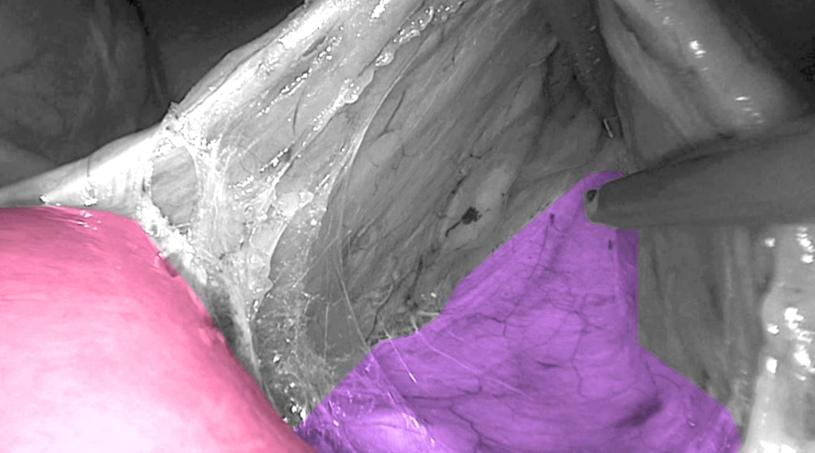

The first step is to divide the attachments to the duodenum and identify the VMI. The VMI is orientated horizontally by manipulating the 30° camera. In a line parallel to and just under the inferior mesenteric vein dissection is started from medial to lateral. By identifying Gerota’s fascia and staying in the submesocolic plane an almost bloodless dissection can be performed.

Toldt’s fascia in purple and Duodenum in pink.

(Copyright Dr. Joep Knol)